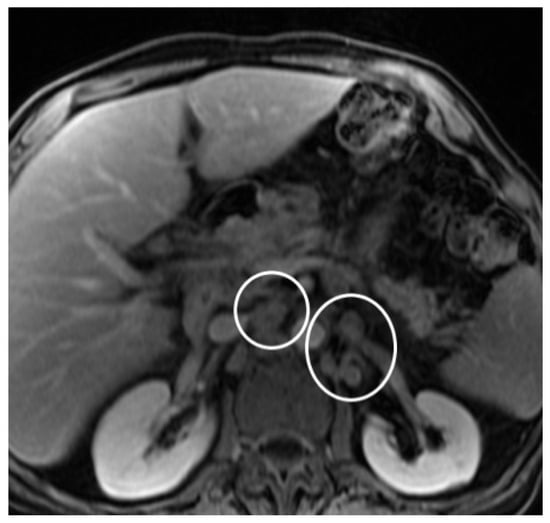

2. Case Report